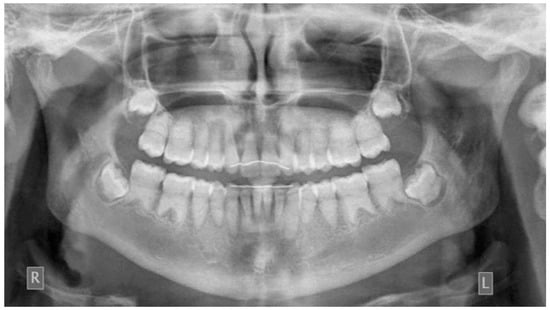

The pre-treatment panoramic radiograph revealed short root length of most of the teeth, delayed tooth eruption, obliteration of pulp chambers and periapical radio-lucencies, not associated with periodontal disease or pulp inflammation. Horizontal crescent-shaped lines along the cementoenamel junction were evident in several teeth. Based on radiographic characteristics, this patient was subclassified as DD-Ic [10]. The permanent maxillary canines were impacted (Figure 1). Pre-treatment cone-beam-computed-tomography scans showed that the upper right maxillary canine (#13) was labially impacted; the contralateral canine (#23) displayed a more palatal position. Both teeth were above the roots of the adjacent lateral incisors, in close proximity to them and to the roots of the central incisors (Figure 2). Sclerosis of the maxilla and the mandible was absent in this case, as well as in the skeleton (Figure 3).

Figure 2. Pre-treatment panoramic radiograph and Cone Beam Computed Tomography 3D reconstruction of the maxilla, showing the impacted upper canines (R: right, L: left, upper canines displayed in red).